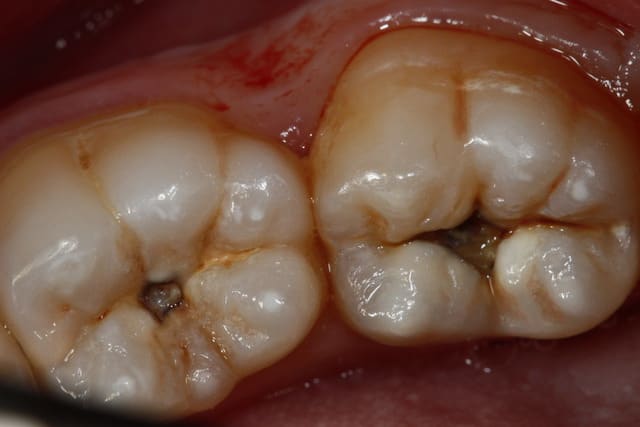

On relance, 2 compos tous frais, c'est basique mais ça me fait plaisir, en 35 minutes avec le détartrage on est presque au taux horaire, pas de stress...

Photos un peu floues, j'ai prêté mon miroir occlusal, désolé.

Img 2760 y33qry - Eugenol

Img 2759 ohq0n5 - Eugenol